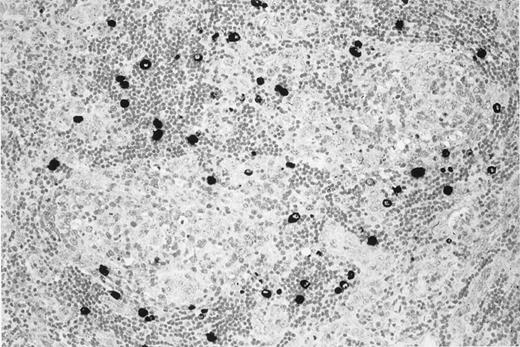

KSHV v–IL-6 expression in a lymph node of the patient with multicentric Castleman disease.

MCD lymph node section showing KSHV v–IL-6 expression (black) restricted to lymphocytes in the mantle zone of lymphoid follicles.